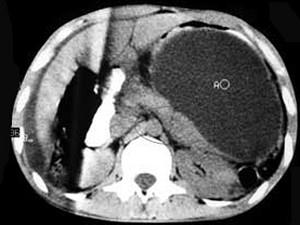

问题 男,33岁,腹部外伤后两月余,腹部疼痛,行CT扫描所见如图,最可能的诊断是 ( )

选项 A、畸胎瘤 B、腹腔包裹性积血 C、慢性胰腺炎 D、胰腺创伤性假性囊肿 E、急性胰腺炎

答案 D